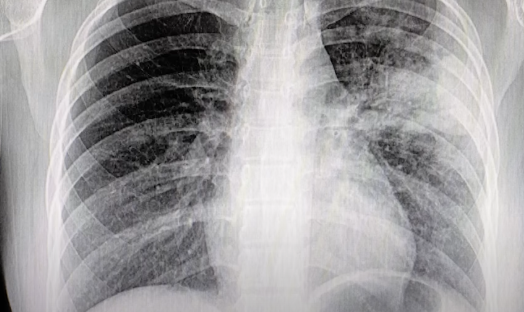

반응형 폐렴 예방법1 폐렴 증상부터 원인, 예방법까지 🌬️ 반드시 알아야 할 폐 건강 정보 폐렴의 증상, 원인부터 정확한 진단과 치료, 예방접종 정보까지 한눈에 정리했습니다. 고령자와 가족이 꼭 알아야 할 폐렴 예방과 관리법을 확인해보세요! 최근 계절 변화와 미세먼지, 감염병 유행으로 ‘폐렴’에 대한 관심이 부쩍 높아지고 있습니다. 실제로 국민건강보험공단 통계에 따르면 2024년 폐렴 환자 수는 작년 대비 약 15% 증가했으며, 특히 60세 이상 고령층에서 위험성이 높아지고 있습니다. 폐렴은 감기처럼 가볍게 여기기 쉽지만, 심할 경우 생명까지 위협하는 치명적인 호흡기 질환입니다. 오늘은 폐렴의 증상과 원인, 예방법까지 전문가 의견과 최신 자료를 참고해 정리해보겠습니다. 폐렴이란 무엇인가요? 🩺폐렴은 바이러스, 세균, 곰팡이 등에 의해 폐에 염증이 생기는 질환입니다. 폐포(공기주머니)에 염증.. 2025. 4. 22. 이전 1 다음 반응형